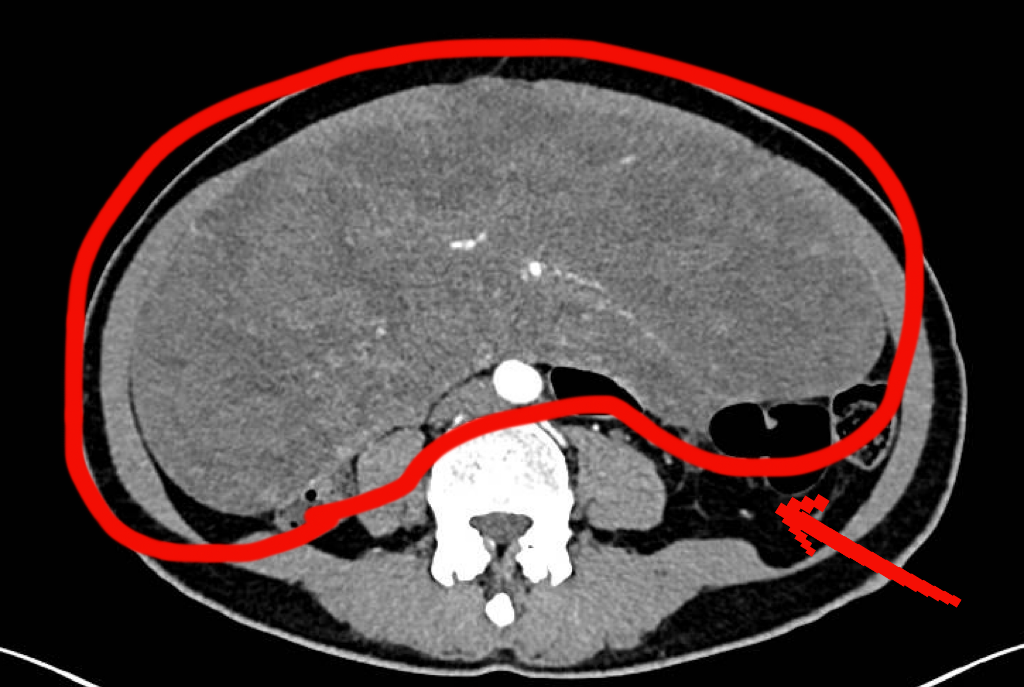

CT显示,洪女士的子宫前有一个巨大的肿块,医生判断可能是由多个肌瘤融合形成的巨大子宫肌瘤。

洪女士的CT检查图像